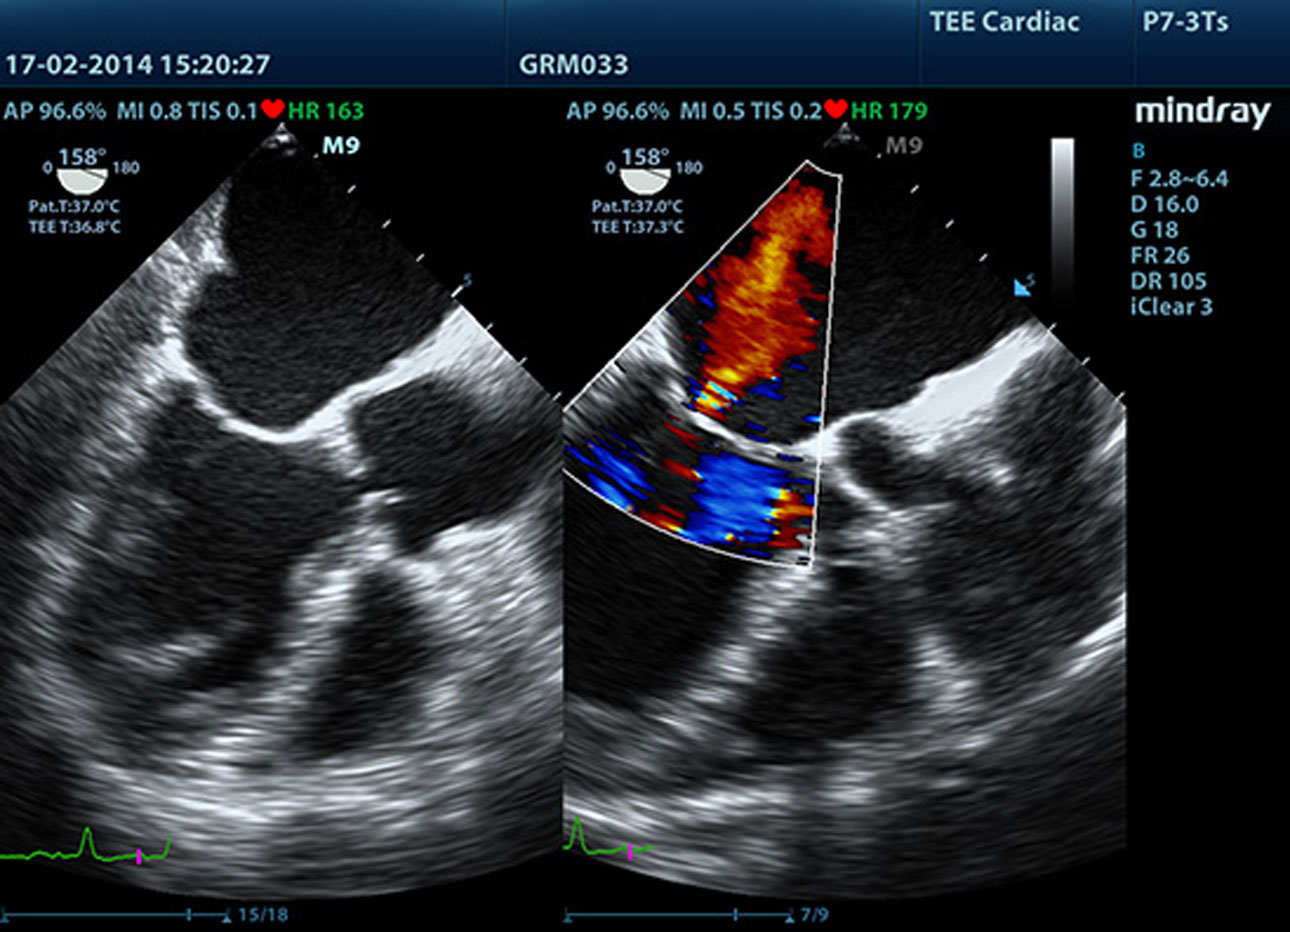

TDI

Met Tissue Doppler Imaging kunt u de plaatselijke myocardbeweging en -functie kwantitatief evalueren met volledige TDI-modi voor snellere en directe diagnoses.